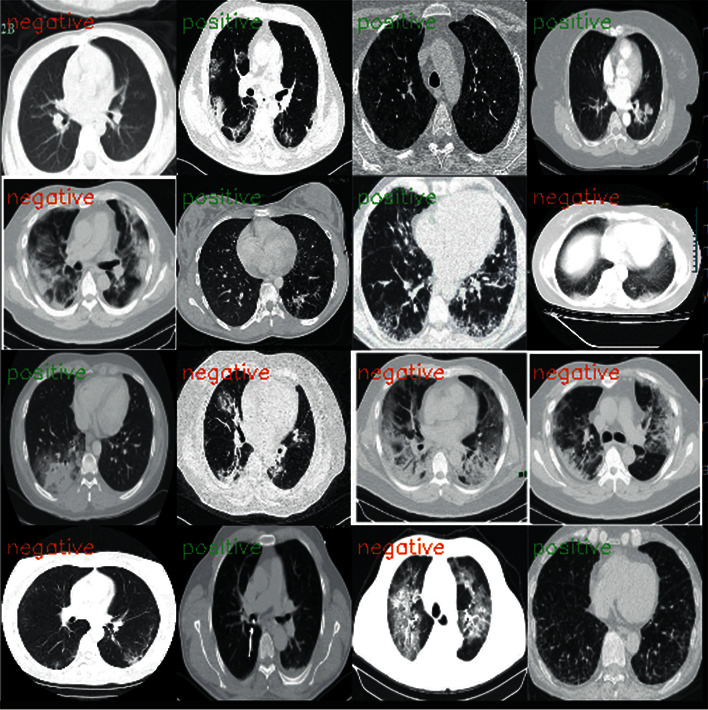

Our main goal here is to achieve good results in detecting COVID-19 cases. In this work, the datasets are gathered into two subsets, 80% for training and 20% for testing, including normal and COVID-19 cases. Figure 4 shows the CT and X-ray images.

Figure 4.

Example of X-ray and CT images of a normal patient and a COVID-19 patient.

Figure 8 shows the accuracy and loss curves on the training and validation processes to evaluate the performance of the proposed VGG19 network. The achieved training and validation accuracy rates are 86% and 77%, respectively. Similarly, the training and validation loss values are 0.32 and 0.41, respectively, for the proposed model. For the testing phase, we tested our trained model to evaluate the VGG19 classifier for the detection of COVID-19 and normal cases on the CT dataset, as illustrated in Figure 9.

Figure 9.

Tested VGG19 model.